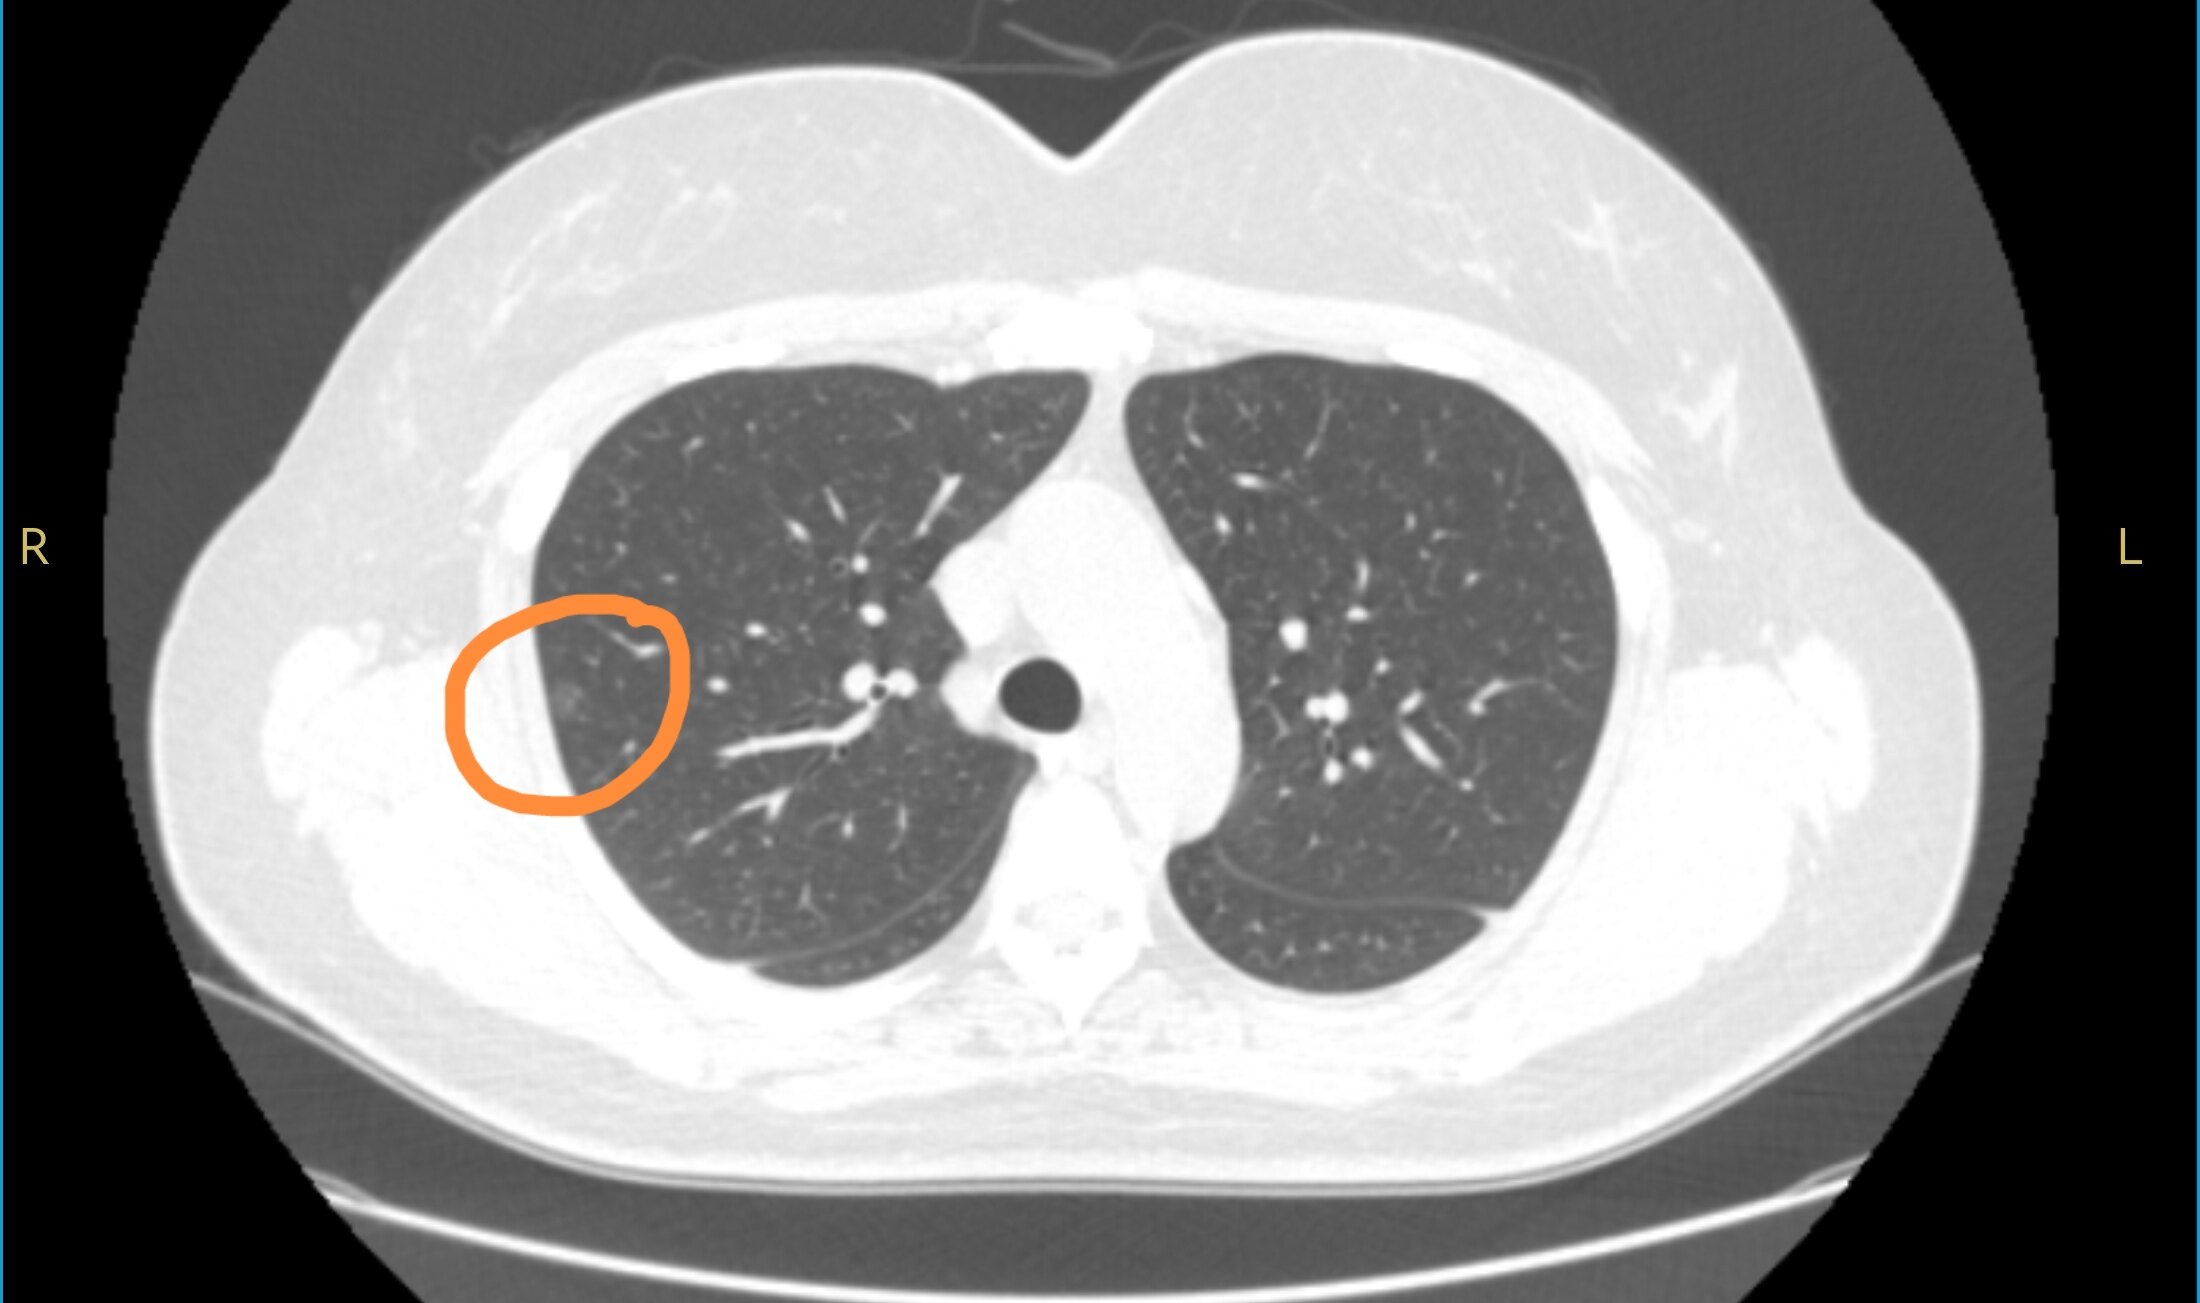

╯﹏╰ 盘点早期肺癌诊断的关键指标,一文全掌握!1. 肿瘤标志物 肿瘤标志物就像是肺癌在身体里留下的“小尾巴”。比如癌胚抗原(CEA),它在很多肺癌患者体内会升高,就像是一个“警报器”。还有神经元特异性烯醇化酶(NSE),对小细胞肺癌有较高的诊断价值,这波监测肿瘤的操作直接封神。不过,肿瘤标志物升高也不一定就得了肺癌...